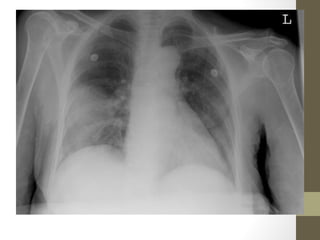

• CXR—useful in upper quadrant pain

Radiographic Studies: Other •CXR—useful in upper quadrant pain • ERCP—essential for common duct obstruction (gallstones, sludge, compression, stricture)

Case #2 - Interventions/Diagnosis •CXR reveals intra-abdominal free air • Diagnosis: Perforation, likely duodenal or gastric ulcer • Disposition: To OR for identification and repair

Rapid Case #6 •32 yo female, S/P Tubal ligation 2 weeks ago • Gradual onset diffuse pain • N/V/D, fever • Diffusely tender, guarding, + rebound • CXR with free air • Bowel perforation

Do you seethe free air?